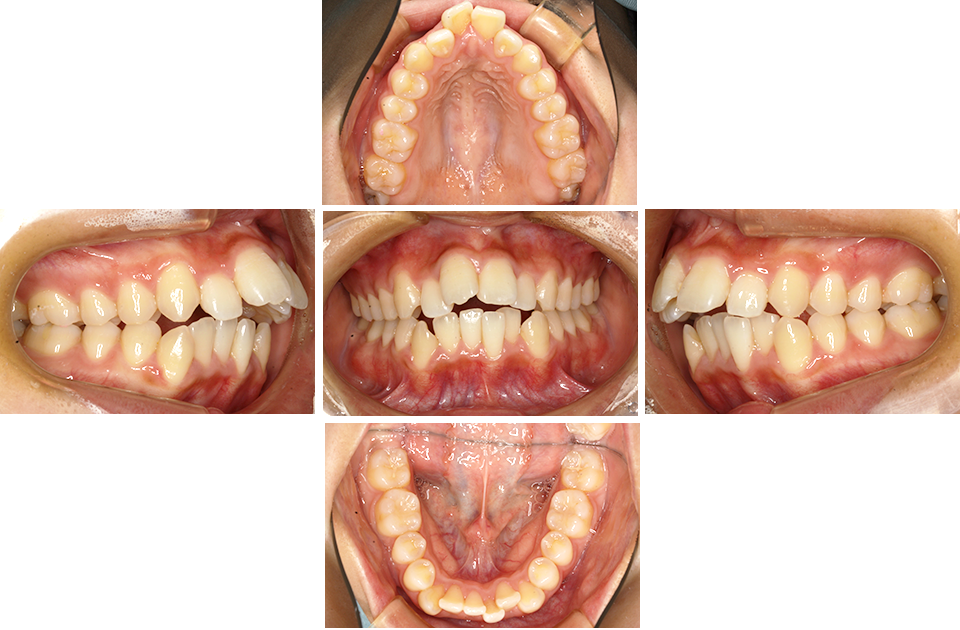

上顎前突 抜歯症例

EXTRACTION CASE OF MAXILLARY PROTRUSION

矯正前

矯正前 正面

矯正前 右側

矯正前 左側

矯正前 上顎

矯正前 下顎

主訴 前歯で物が咬めない、歯並びの凸凹、出っ歯を治したい

年齢 20代

治療法 上下顎マルチブラケット装置、歯科矯正用アンカースクリュー

抜歯の有無 上顎左右側第一小臼歯、下顎左右側第二小臼歯

治療期間 1年10ヶ月